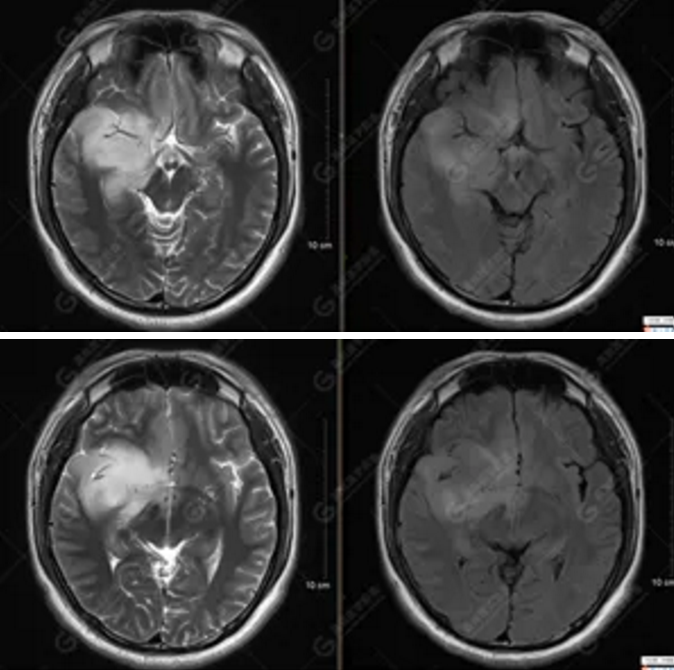

MR影像圖

【MRI平掃及增強(qiáng)檢查所見(jiàn)】右側(cè)額顳島葉、右側(cè)海馬及右側(cè)基底節(jié)區(qū)見(jiàn)一團(tuán)塊狀異常信號(hào)影,累及右側(cè)下丘腦及視交叉,大小約5.1cm×4.5cm×4.3cm,呈長(zhǎng)T1長(zhǎng)T2信號(hào),F(xiàn)LAIR序列呈等、稍高信號(hào),DWI序列呈稍高信號(hào),ADC圖高信號(hào),增強(qiáng)后無(wú)明顯強(qiáng)化;病灶周?chē)?jiàn)片狀長(zhǎng)T1長(zhǎng)T2水腫信號(hào)影,F(xiàn)LAIR序列呈高信號(hào),病灶內(nèi)見(jiàn)右側(cè)大腦中動(dòng)脈穿行。余腦實(shí)質(zhì)內(nèi)未見(jiàn)局灶性信號(hào)異常,增強(qiáng)后未見(jiàn)異常強(qiáng)化。右側(cè)側(cè)腦室輕度受壓,余腦室、腦池大小、形態(tài)均正常,中線(xiàn)結(jié)構(gòu)居中